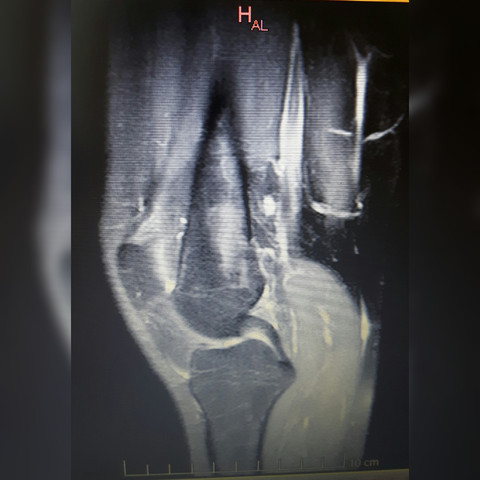

Tumor im knie mrt. Es kann jedoch ausreichen für eine erste Verdachtsdiagnose. Daher sollten alle Patienten bei denen ein primärer bösartiger Knochentumor vermutet wird an einen Experten bzw. Per MRT wurde ein Riesenzelltumor im Knie.

In bildgebenden Verfahren wie Röntgen Szintigraphie Computertomographie CT oder Magnetresonanztomographie MRT können Veränderungen gesehen werden ebenso kann vor einer Behandlung die Ausdehnung beurteilt werden. Steht die Diagnose Knochenkrebs fest fahndet Ihr Radiologe nach Metastasen. Häufig ist zur weiteren spezifischen Abklärung eine zusätzliche Bildgebung mittels Kernspintomographie MRT erforderlich.

Magnetresonanztomographie mrt bei der magnetresonanztomographie wird die magnetisierung von wasserstoffatomen die in biologischem gewebe überall vorhanden sind durch einstrahlen einer radiowelle geändert. Hierdurch kann zudem die Ausdehnung innerhalb des Knochens sowie eine mögliche Beteiligung von umgebenden Strukturen sichtbar gemacht werden.

MRT des Kniegelenkes Anatomie. Mit einem bildgebenden verfahren wird genau ermittelt wo der tumor im kopf liegt. In bildgebenden Verfahren wie Röntgen Szintigraphie Computertomographie CT oder Magnetresonanztomographie MRT können Veränderungen gesehen werden ebenso kann vor einer Behandlung die Ausdehnung beurteilt werden. Für das ungeübte Auge ist der Tumor auf einem einfachen Röntgenbild schwer zu identifizieren. Je nach Sequenz kann man im MRT das Synovialsarkom sehr gut gegenüber dem Muskel oder Fettgewebe abgrenzen. Hierdurch kann zudem die Ausdehnung innerhalb des Knochens sowie eine mögliche Beteiligung von umgebenden Strukturen sichtbar gemacht werden. Er verabreicht Ihnen eine gesundheitlich unbedenkliche Menge einer radioaktiven Substanz die sich in Krebszellen einlagert. Es erfolgt die Befragung des Patienten Anamnese sowie eine körperliche Untersuchung. Dazu nutzt er neben CT und MRT auch die sogenannte Skelettszintigrafie.